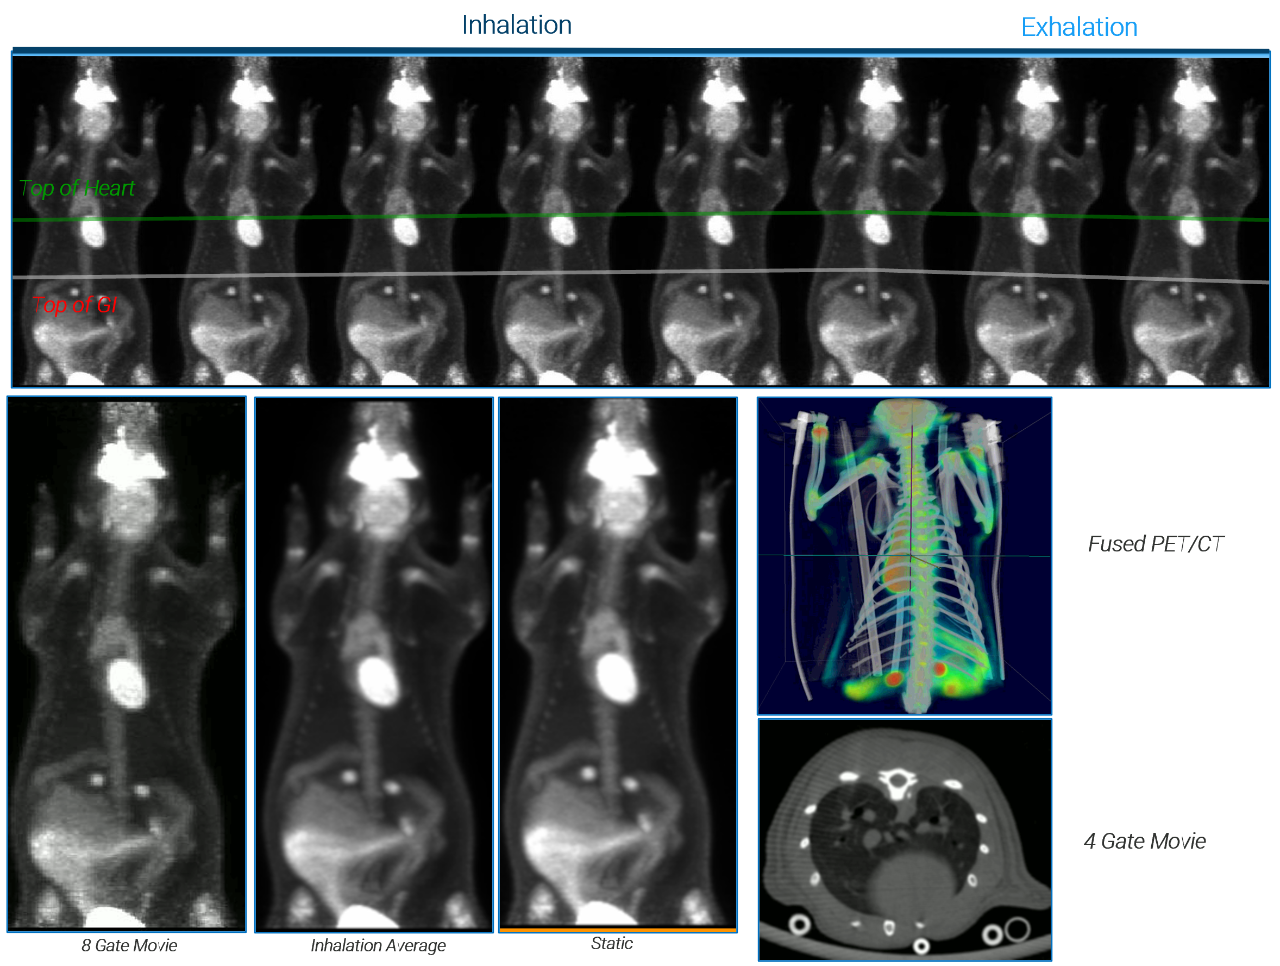

Mice Pulmonary

Cardiovascular Imaging

Total Body PET Capabilities